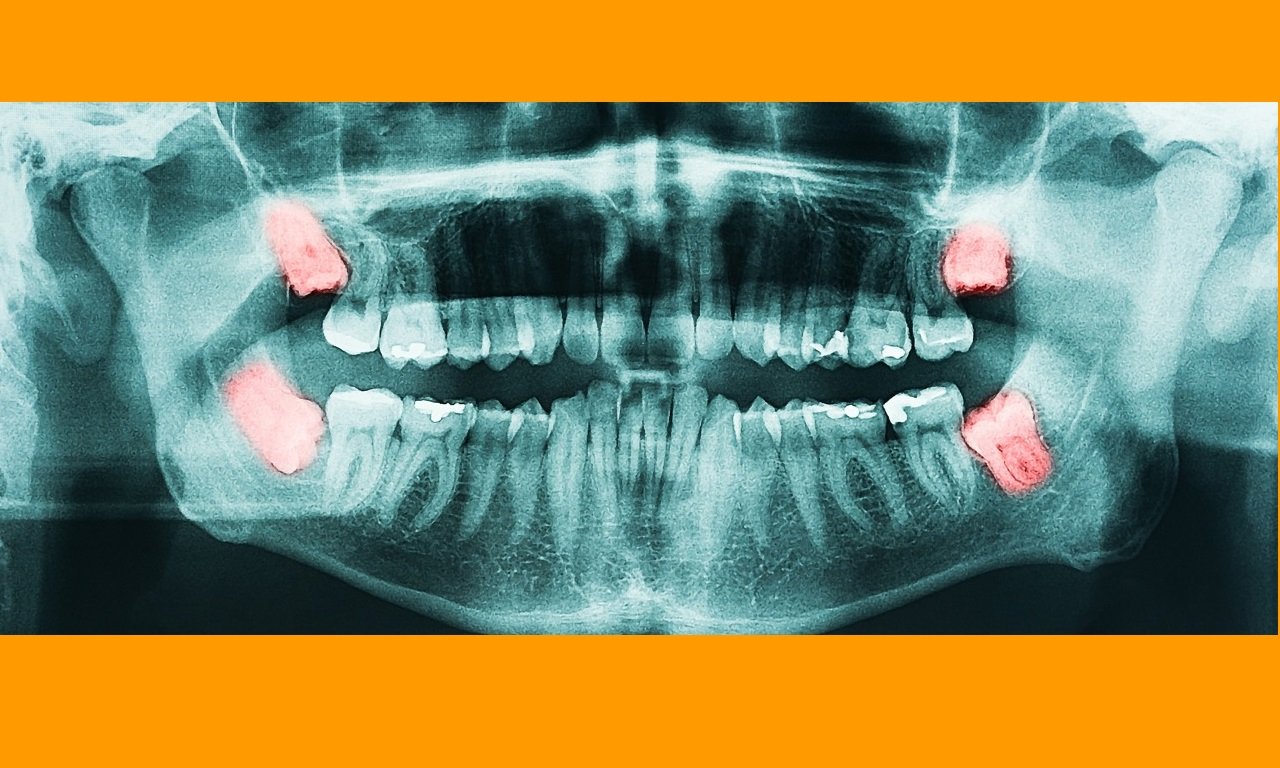

If your wisdom teeth are giving trouble, you may consider to have them removed...